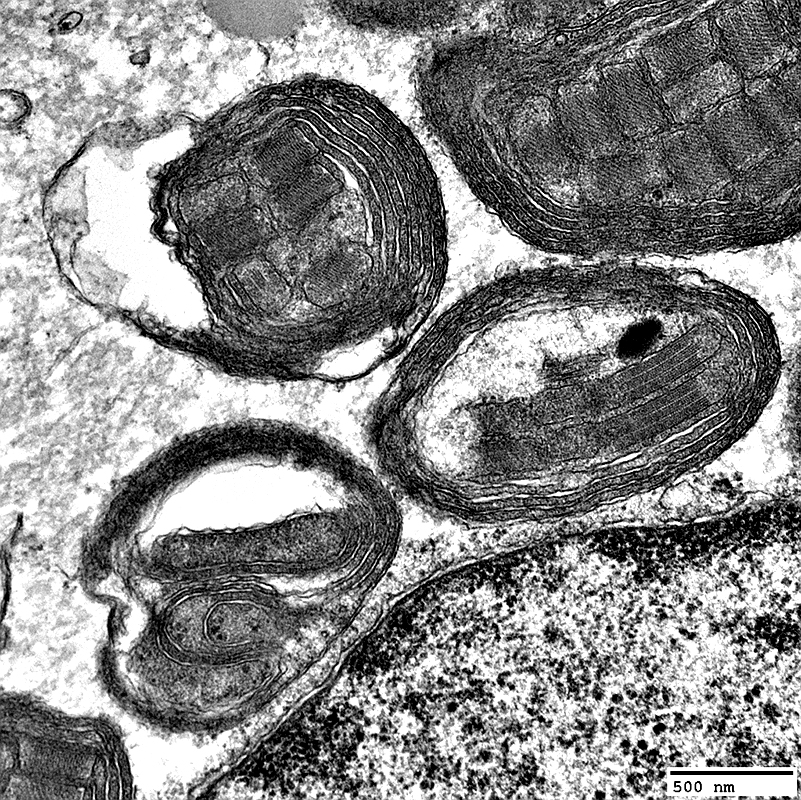

MNGIE: Muscle Ultrastructure

From: R Schmidt